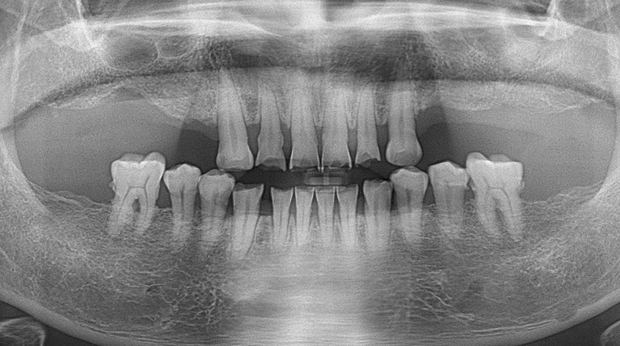

임플란트와 사랑니 발치는 외과적 시술로 잇몸을 절개하는 외과적 시술은

짧으면 짧을 수록 시술 후 붓기와 통증이 최소화됩니다.

치과의사 경력 14년차 구강외과 전문의가 빠르고 안전하게, 아프지 않게 수술해 드립니다.

치과경력 14년차 구강외과 전문의